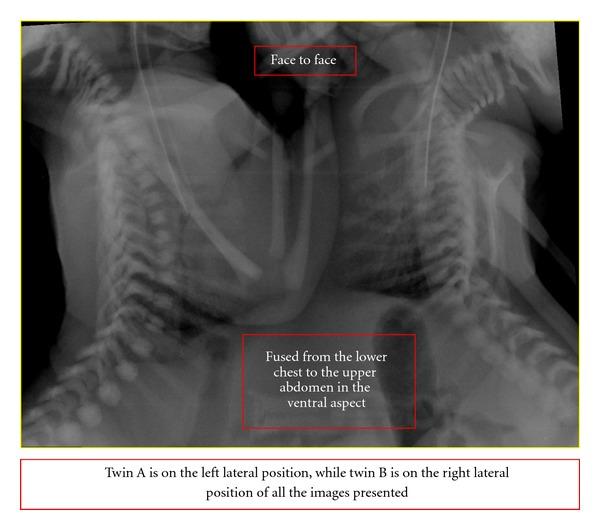

Conjoined twins are rare and present a unique challenge to pediatric surgeons and radiologists. An imaging strategy to accurately define anatomic fusion, vascular anomalies, and other associated abnormalities is important for surgical planning and prognostic information. A conjoined female twin with a combined weight of 2.8 kg was born by emergency caeserean. Hence, a computed tomography scan of the thorax and entire abdomen at 1.25 mm slice thickness was performed to delineate the internal structures of the twins. CT-angiography defined specific vascular supply which determined the distribution of shared structures between the twins. An echocardiogram showed four heart chambers with atrioventricular septal defect. To further evaluate the heart chambers, the twin was planned for gated cardiac magnetic resonance imaging. Unfortunately, they succumbed 6 hours apart due to complication of septicemia. Magnetic resonance imaging and CT scan provide excellent anatomic detail, demonstrating organ position, shared viscera, and limited vascular anatomy, whilst angiography defined specific vascular supply, useful in determining the distribution of shared structures between the twins in planning for surgery.